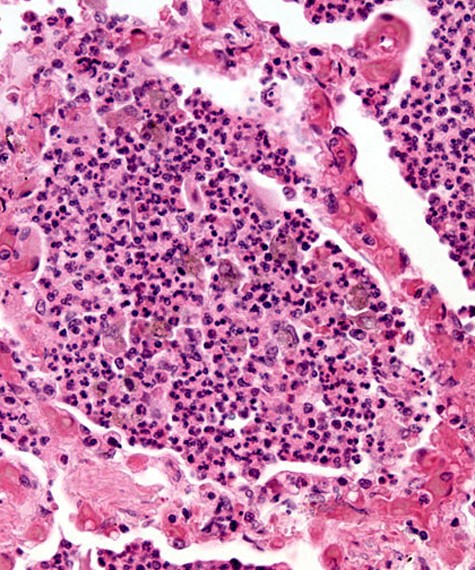

Upon taking my patient’s history, I found that Aliyu presented with a fever, headache, general body weakness and pain, nausea, and vomiting. I requested a Rapid Diagnostic Test (RDT) which came back positive allowing me to diagnose the patient with malaria. I prescribed Aliyu Artemether-Lumefantrine, which is an anti-malarial tablet and advised him to wear long sleeves, pants, and to sleep using an insecticide-treated mosquito net to prevent catching malaria again.